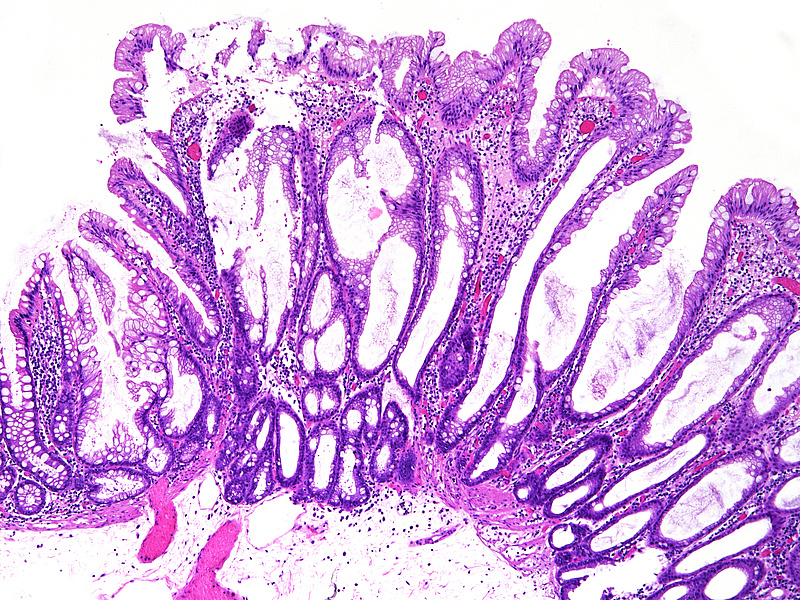

The ascending colon polyp is a serrated polyp characterized by a combination of two morphological patterns which are sessile serrated lesion (SSL) and traditional serrated adenoma (TSA). The former is formed by architecturally distorted serrated crypts with deep serrations, basal crypt dilatation and lateral growth along the muscularis mucosae (Panels A-B). Some foci of stromal proliferation resembling perineural cells are also seen within this component (Panel C). The TSA component has typical slit-like serrations, lined by tall columnar cells with intensely eosinophilic cytoplasm and pencillate nuclei (Panels D-E). Abrupt transition to dysplastic mucosa and glands are present, where the glands display more complex and crowded architecture with little intervening lamina propria (Panel F). The dysplastic cells show features of adenomatous dysplasia characterized by columnar cells with enlarged hyperchromatic nuclei, pseudostratification and reduced goblet cells (Panel G). In some areas, the cells display high grade cytology with more rounded nuclei and loss of polarity. MLH1 immunostaining was preserved in both the non-dysplastic and dysplastic glands with higher intense staining seen in the latter (Panel H).